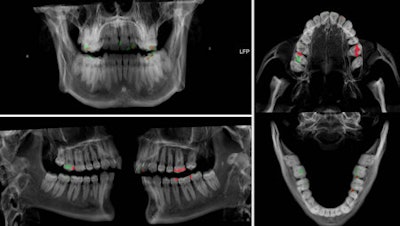

A case in point is the visualization of dental fillings. Dental x-ray plays a key role alongside DNA in identifying human remains whether in mass fatalities or single incidents when bodies have undergone alteration after death. Up to 80% of postmortem identification in the wake of the Asian tsunami in 2004 was based on dental status. Ultrahigh-resolution dual-source CT with extended CT scale has proved to reduce streak-induced artifacts and distinguish between fillings, whether composite, amalgam, ceramic, or temporary fillings, based on radiopacity in Hounsfield units, their size, and location.

Using a Siemens Healthcare Definition Flash, Jackowski has dedicated the past year of ongoing research to the development of a dual-energy application of more than 30,000 Hounsfield units and a software tool to analyze the data obtained to further characterize filling materials. This development could have implications for other areas of postmortem imaging such as bullet characterization.